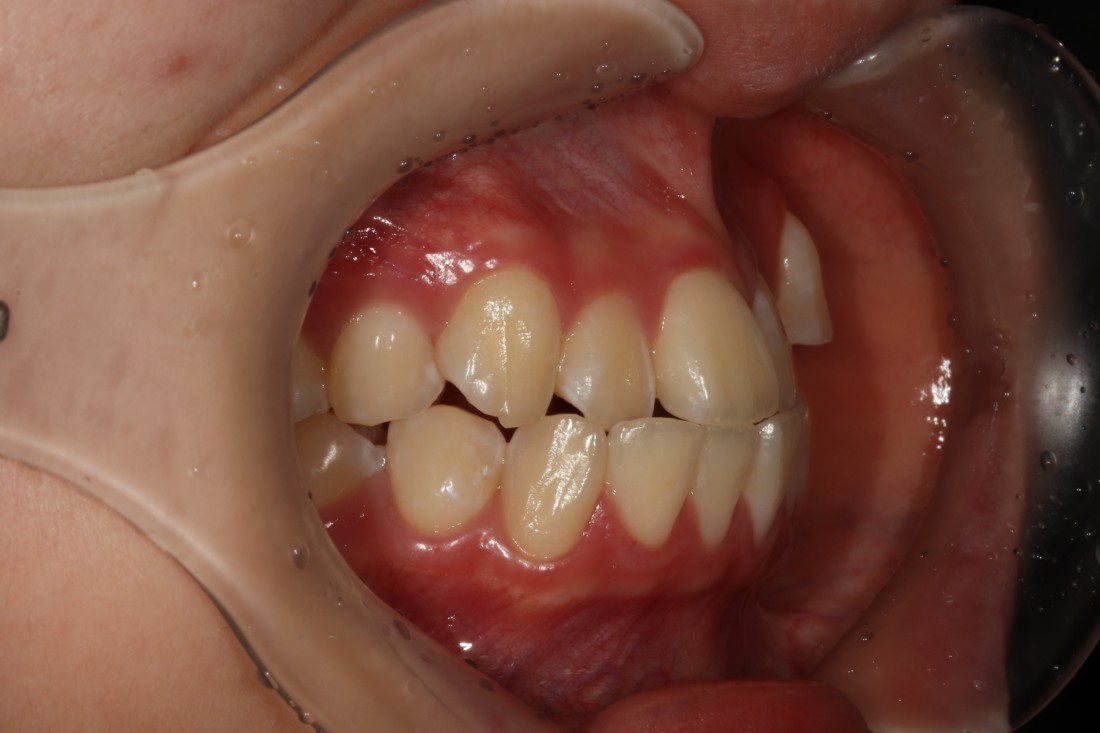

수완동 교정치과,

교정전문의 대표원장 진료

확인하셨나요?

수완동 교정치과를 선택할 때는

경험많은 교정전문의 대표원장이

세밀한 상담부터 치료계획,

월 정기진료 및 교정 후 관리까지

꼼꼼하게 책임지고 관리하는

교정치과인지 확인하는 것이

가장 중요합니다.

서울우리아이치과는

4층 교정진료센터에서

교정진료만을 전담으로 맡아서 하는

교정전담팀이 상주하고 있습니다.

오직 단 한 분만을 위해 운영되는

1인 교정 룸 진료실에서

프라이빗하게 수완동 치아교정을

받으실 수 있습니다.